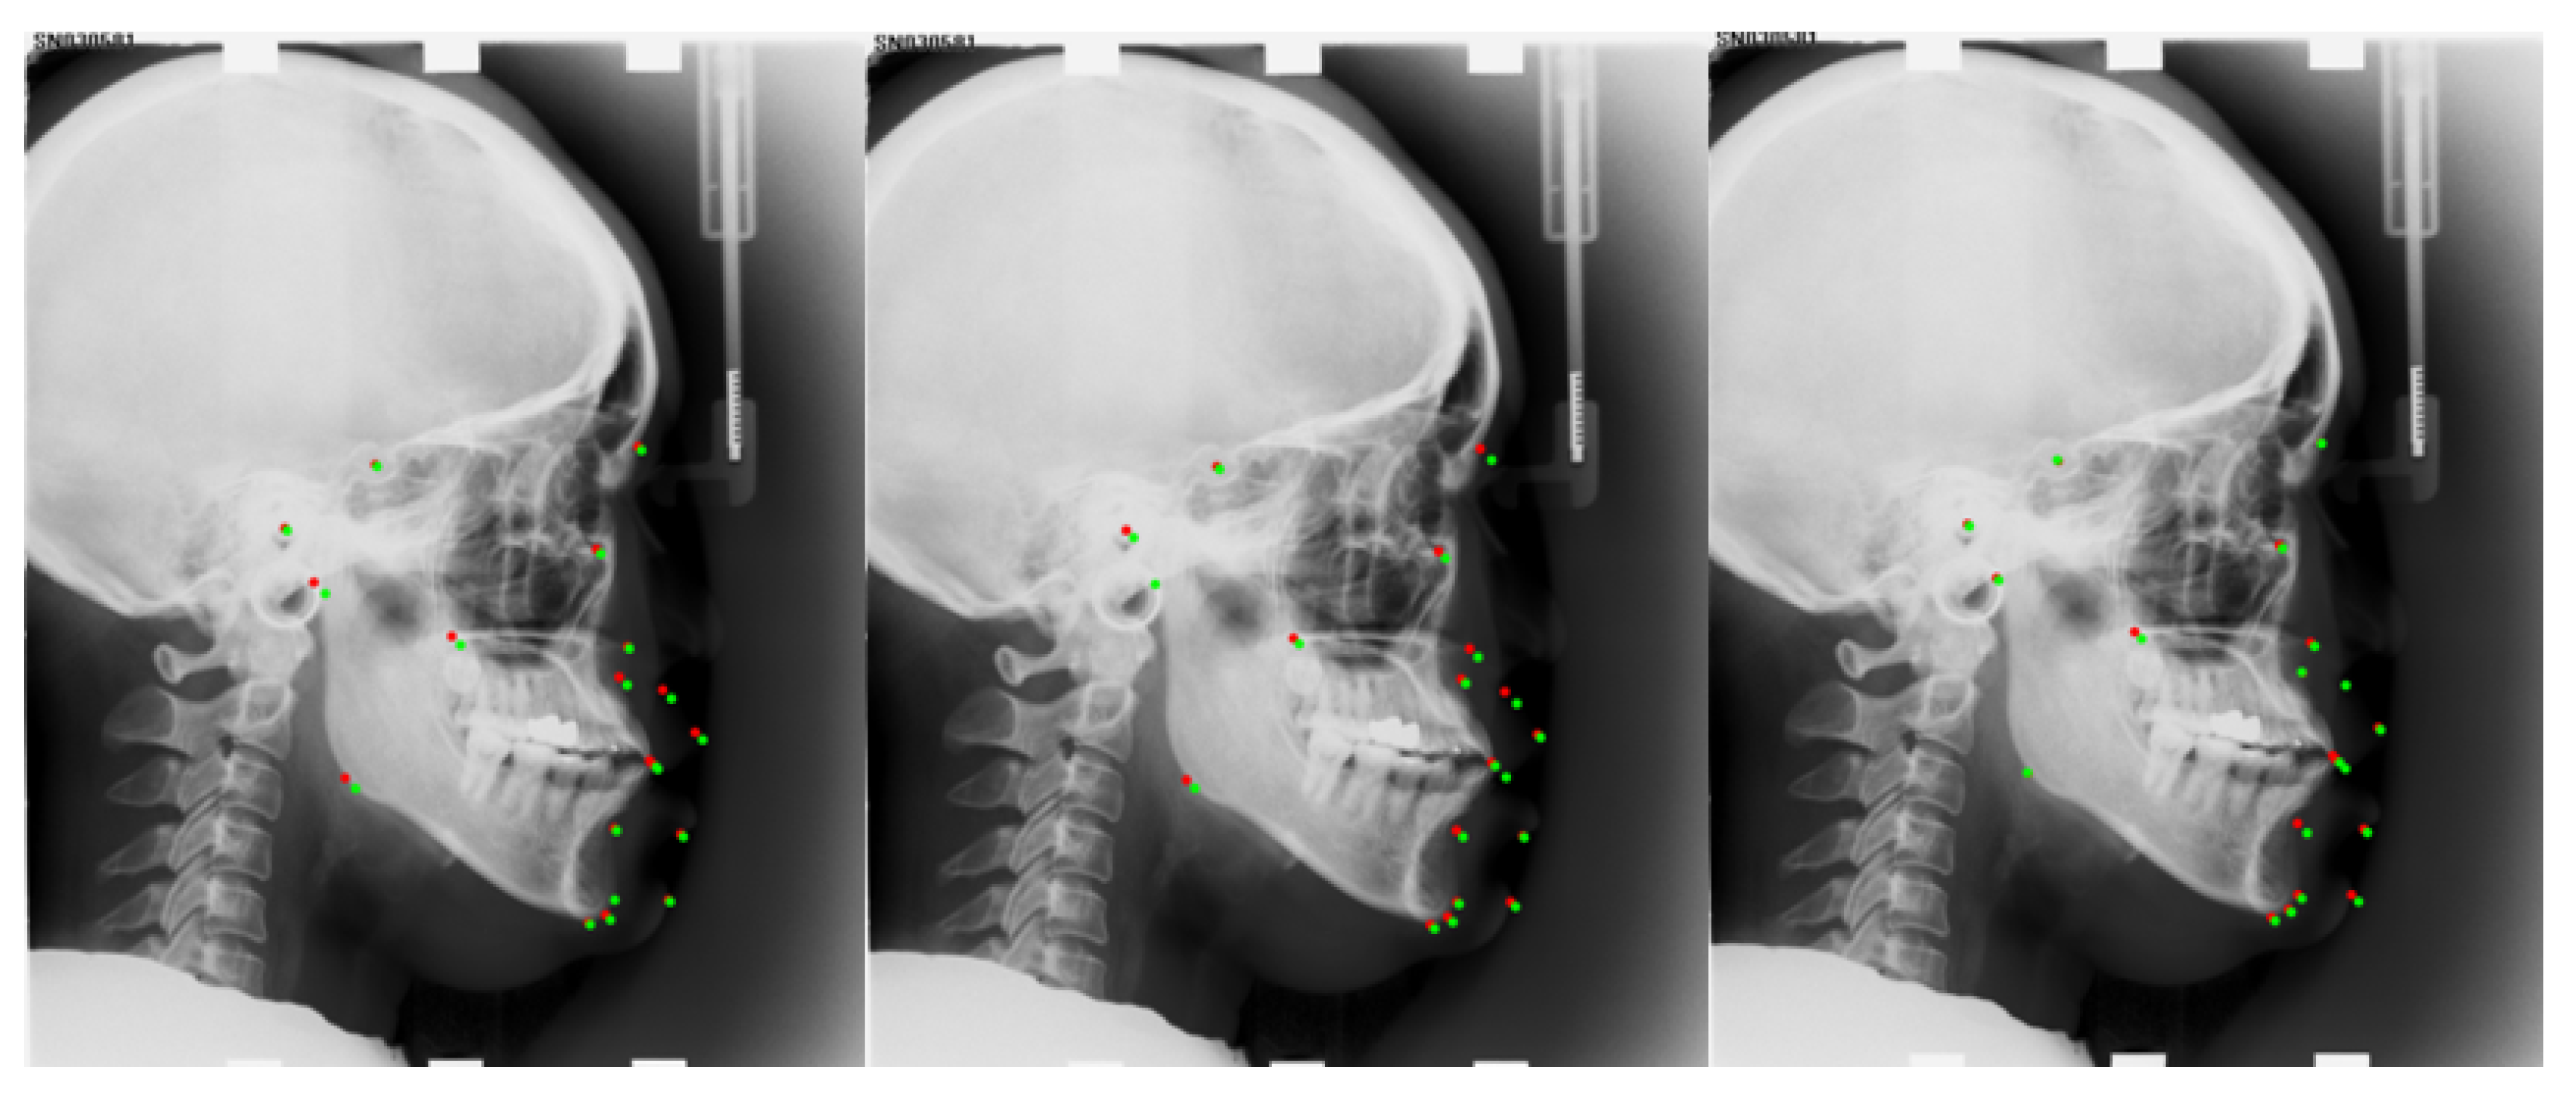

| Number | L1 | L2 | L3 | L4 | L5 | L6 | L7 | L8 | L9 | L10 |

| Anatomical Name | Sella | Nasion | Orbitale | Porion | Subspinale | Supramentale | Pogonion | Menton | Gnathion | Gonion |

| Number | L11 | L12 | L13 | L14 | L15 | L16 | L17 | L18 | L19 | |

| Anatomical Name | Lower incisal incision | Upper incisal incision | Upper lip | Lower lip | Subnasale | Soft tissue pogonion | Posterior nasal spine | Anterior nasal spine | Articulate |